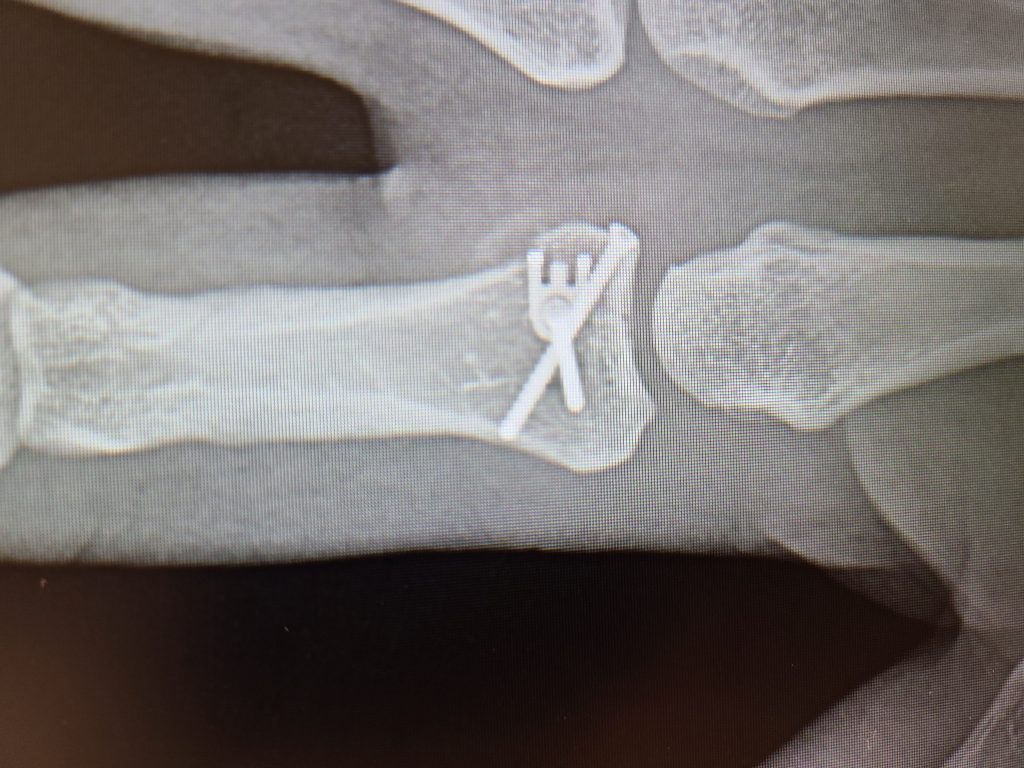

My story begins when my finger was broken one night in April. Wow, that was painful! I then went to the ER and after a couple of x-rays, they confirmed my finger was actually broken. The next phase was to find the best doctor to help fix my broken finger. I had previously been to HSS for my knee and thought there is nowhere else I would go other than HSS. I went through the HSS directory and after a few phone calls to inquire I zeroed in to meet with Dr. Save. I was very impressed with his experience and even more impressed when I met him. I told Dr. Save that I am an avid firearms shooter and that I've been shooting for over 20 years. I take part in shooting competitions all throughout the year and THE most important part of my body is my trigger finger! Dr. Save said that he has a plan to help me get back on track, and I had full confidence that he will. After I woke up from the surgery, he said that it went very well and that we need to start on the road to recovery. I met with Dr. Save all throughout the healing process and each time we met, he was impressed with how well the surgery went and how my finger was healing. Today, I am Back in the Game! I'm at the range every weekend and enjoying every minute of it. My finger is back to normal, I have full range of motion, no pain whatsoever and more importantly my quality of life is back to normal as well. I have 3 small children at home and the day to day of being a dad, a husband, a homeowner and an avid marksman, everything came back to the way it was. I wanted to share my story to let everyone know how thankful I am for Dr. Save and thankful he helped me get back to the things I love the most in life with his incredible gift and talent as a surgeon. Thank you, Dr. Save, you SAVED me! And of course, Thank you HSS!